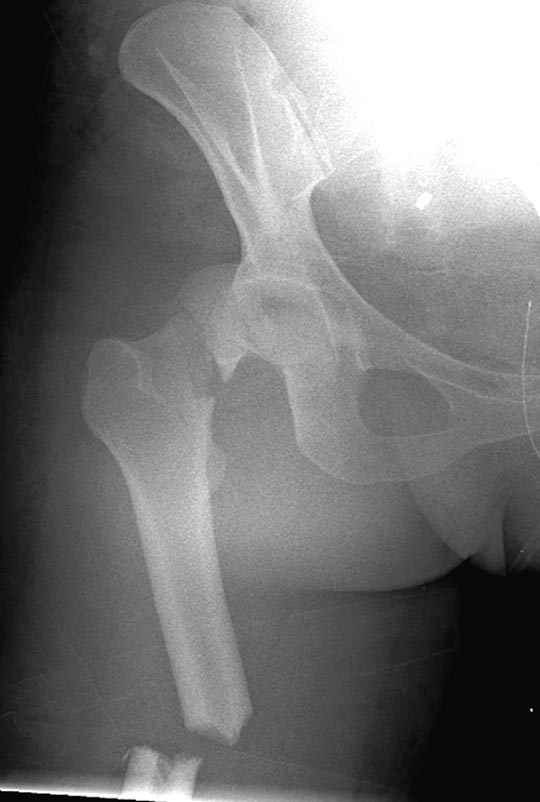

Вложение не в текстовом формате было извлечено…

Имя     : Picture2.jpg

Тип     : image/jpeg

Размер  : 43279 байтов

Описание: отсутствует

Url     : http://weborto.net:8080/pipermail/ortho/attachments/20180407/cb9d5034/attachment-0011.jpg